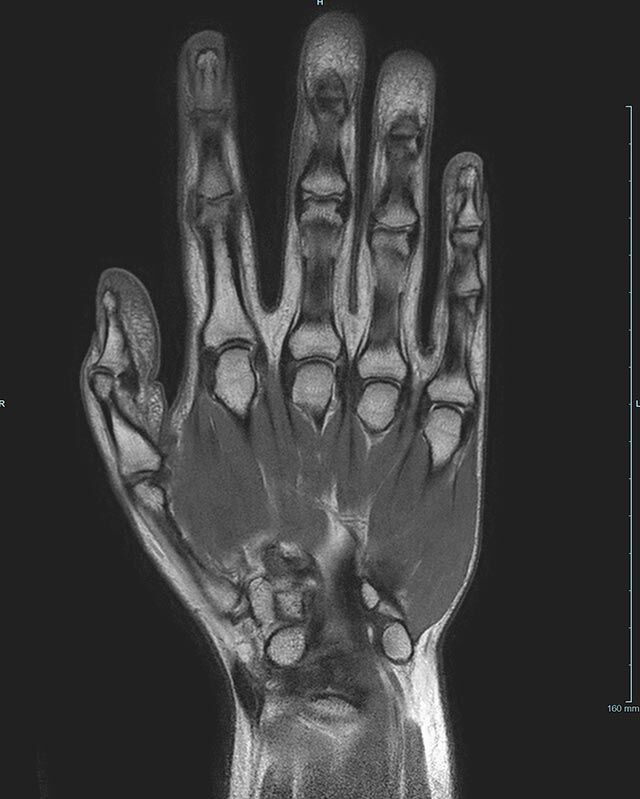

Hand

• Beurteilung von Knochen, Bändern und anderen Weichteilstrukturen der Gelenke nach Unfall.

• Arthrosediagnostik (Knorpelschaden)

• Impingement-Symptomatik

• Ursachenklärung bei wiederholter spontaner Gelenkluxation

• Ausbreitungsdiagnostik bei Gelenkentzündung, z.B. im Rahmen von rheumatischen Grunderkrankungen